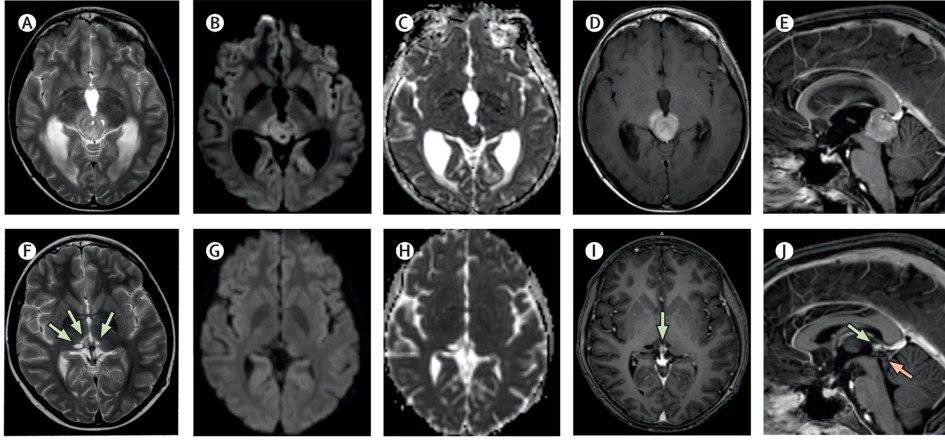

Germinomas in the basal ganglia: magnetic resonance imaging classification and the prognosis.

Early imaging findings in germ cell tumors arising from the basal ganglia.

T2*-based MR imaging (gradient echo or susceptibility-weighted imaging) in midline and off-midline intracranial germ cell tumors: a pilot study.

Susceptibility-weighted imaging in the diagnosis of early basal ganglia germinoma.